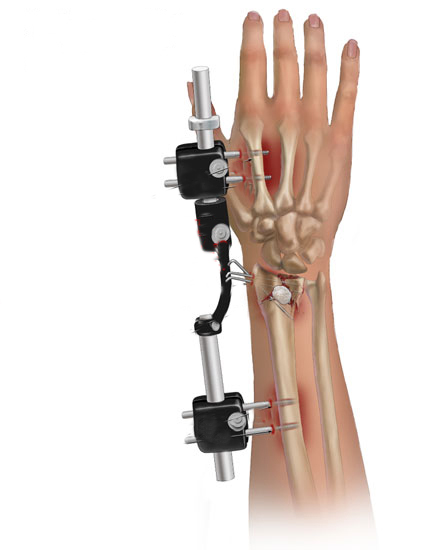

Fissatore Esterno

Per Fissatore Esterno s’intende un mezzo di fissaggio che non viene coperto dalla pelle ma attraverso piccole aste metalliche chiamate “fiches”, che vengono applicate sopra e sotto alla frattura nell’osso e un corpo centrale che serve a stabilizzare la frattura ossea. A volte in base al trauma viene associato ad altri sistemi di fissaggio come ad esempio i fili di Kirschner.

Il fissatore esterno può anche essere un mezzo di sintesi temporaneo ovvero quando la qualità dei tessuti molli è scadente si posizione per poi essere sostituito con un impianto interno come la placca e le viti.

Lo svantaggio di questo sistema chirurgico rispetto all’osteosintesi con placca e viti è l’infezione delle viti metalliche che fuoriescono dalla pelle, l’impossibilità di ridurre accuratamente la frattura e l’impossibilità di eseguire le mobilizzazioni precoci, mentre il vantaggio è la non esposizione della frattura.

![]() |

|

Fissatore Esterno utilizzato nel Cane |

Fissatore Esterno utilizzato nell’Uomo |